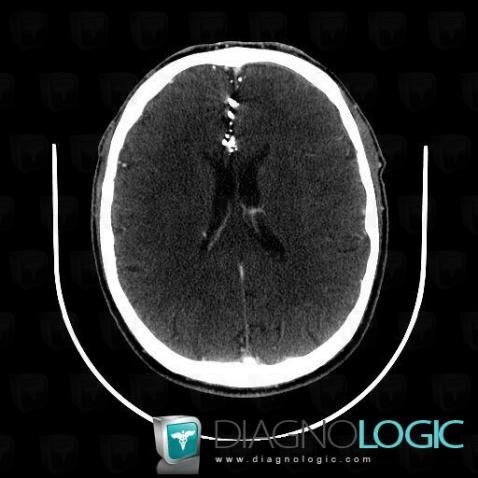

Lipiodol injection, Supratentorial peri cerebral spaces, CT

Here is the specific information in the key image above:

- Diagnosis Lipiodol injection, Location(s) Supratentorial peri cerebral spaces, with gamuts Supratentorial extra axial lesion